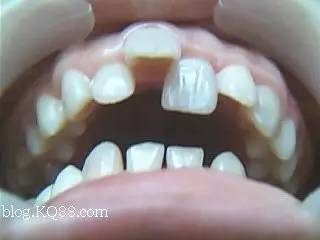

为什么孩子的牙齿总不掉?

这叫乳牙滞留,有些孩子的乳牙在恒牙萌出后还不掉,这种现象为乳牙滞留。家长可以检查一下孩子的乳牙是否松动,如果已经松动可以待其自行脱落,如果丝毫不动,就需要到医院将乳牙拔除。